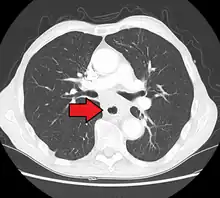

Additional testing is needed to assess how much the cancer has spread (see § Staging, below). Computed tomography (CT) of the chest, abdomen and pelvis can evaluate whether the cancer has spread to adjacent tissues or distant organs (especially liver and lymph nodes). The sensitivity of a CT scan is limited by its ability to detect masses (e.g. enlarged lymph nodes or involved organs) generally larger than 1 cm.[43][44] Positron emission tomography is also used to estimate the extent of the disease and is regarded as more precise than CT alone.[45] PET/MR as a novel modality has shown promising results in preoperative staging with fair feasibility and good correlation in comparison to PET/CT. It can enhance tissue differentiation with lowering the radiation dose to the patient.[46] Esophageal endoscopic ultrasound can provide staging information regarding the level of tumor invasion, and possible spread to regional lymph nodes.

Endoscopy and radial endoscopic ultrasound images of a submucosal tumor in the central portion of the esophagus Contrast CT scan showing an esophageal tumor (axial view)

Contrast CT scan showing an esophageal tumor (axial view) Contrast CT scan showing an esophageal tumor (coronal view)